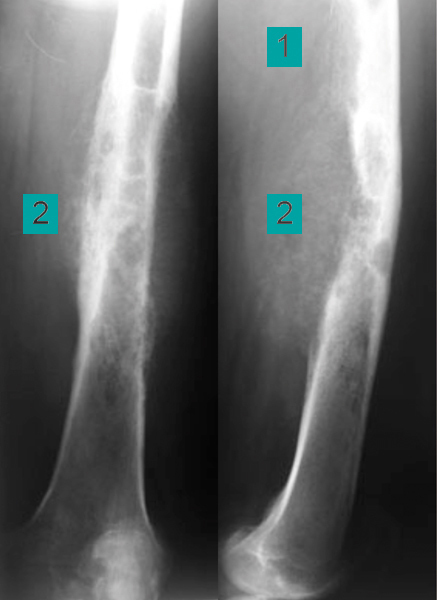

Processus lytique irrégulier au sein de la diaphyse fémorale supérieure

Les corticales sont amincies de façon irrégulière (1), détruites par endroit, avec une effraction dans les parties molles (2). Ces aspects sont très préoccupants et imposent un avis spécialisé en urgence.